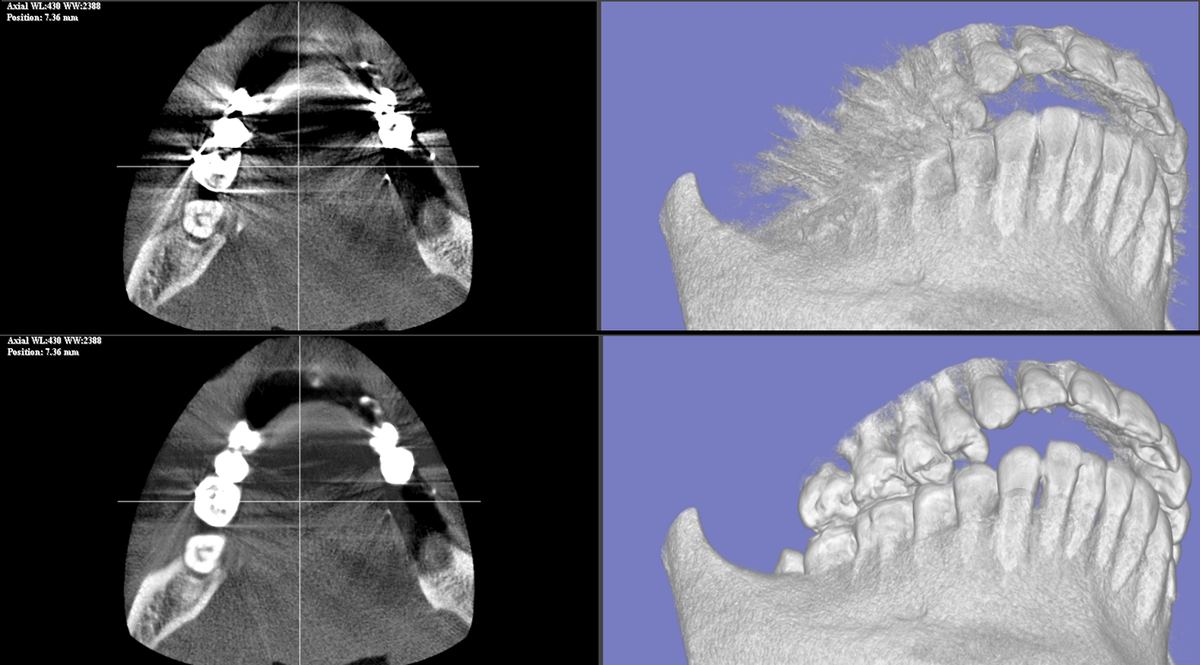

症例 A 上段: Before / 下段: After

D-MAR 症例A Before/After